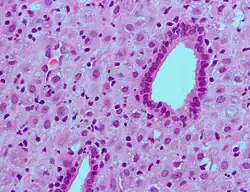

A placenta é uma estrutura em forma de disco que envolve e protege o feto e o líquido amniótico. No termo da gravidez, pesa entre 500 e 1 000 gramas, mede 16 a 20 cm de diâmetro e 3 a 4 cm de espessura. Este órgão encontra-se unido às vilosidades coriónicas que revestem todo o útero, tem aparência lisa e brilhante e é constituída por diversos vasos sanguíneos que se unem no ponto onde começa o cordão umbilical. O sangue materno flui entre os vasos uterinos e o espaço interviloso, onde se acumula. Em cada vilosidade existe uma rede de vasos sanguíneos que fazem parte do sistema circulatório fetal e cuja circulação é impulsionada pelo coração do feto. Esta divisão entre a circulação materna e fetal denomina-se barreira placentária. À medida que a gravidez avança, a barreira torna-se mais fina. Esta barreira impede a passagem de células sanguíneas e de bactérias, embora permita a passagem de nutrientes, sal, vírus, hormonas e diversas substâncias, entre as quais drogas nocivas ao feto.[1]

A alteração mais perceptível no sistema circulatório é o abrandamento da circulação sanguínea nos membros inferiores, o que leva ao aumento da pressão nas veias e estagnação do sangue nas pernas. Estas alterações são provocadas pela compressão da veia cava inferior pelo útero e pelo aumento da produção de hormonas. Embora sejam cada vez mais proeminentes ao longo da gravidez, podendo causar varizes e inchaço das pernas, estas alterações geralmente desaparecem após o parto. A pressão do útero em crescimento nos vasos linfáticos da pélvis provoca a diminuição da drenagem linfática das pernas, o que causa inchaço e dilatação das pernas e pés. O inchaço generalizado noutras partes do corpo é geralmente um sinal de alarme. O volume plasmático aumenta progressivamente a partir da sexta semana e o volume de hemácias aumenta depois da oitava semana. Ambos os volumes tornam-se estáveis nas últimas semanas, mas, como o aumento do volume plasmático é mais precoce e tende a ser mais acentuado do que o aumento do volume de hemácias, ocorre um efeito de diluição responsável pela chamada anemia fisiológica da gravidez. A alteração dos fatores de coagulação prepara o organismo da mulher para o momento do parto, permitindo controlar rapidamente eventuais hemorragias, embora durante a gestação e puerpério aumente o risco de trombose.[1][48]

No termo da gravidez, a quantidade de sangue de uma mulher grávida é aproximadamente 25% superior em relação ao estado de não gravidez, de modo a preencher os vasos do útero, a transportar uma maior quantidade de oxigénio e nutrientes para o feto e servir de reserva em caso de hemorragias. Este aumento é consequência do aumento do número de glóbulos vermelhos (20%) produzidos na medula óssea e pelo aumento do volume do plasma (30%), causado pela retenção de líquidos. Esta diferença de valores faz diminuir a viscosidade do sangue e causa uma anemia aparente.[1]

Alterações metabólicas

O fígado é responsável por muitos dos processos metabólicos vitais, incluindo a eliminação das substâncias nocivas produzidas pelos processos metabólicos do feto. Durante a gravidez, aumenta de tamanho e peso e os seus vasos sanguíneos dilatam, ajustando-se à maior quantidade de hormonas e glóbulos vermelhos em circulação no sangue. A taxa metabólica basal começa a aumentar a partir do terceiro mês, de modo a responder às necessidades conjuntas da mãe e do feto. O corpo da grávida necessita de maior quantidade de nitrogénio, obtido a partir do metabolismo das proteínas ingeridas e fundamental para o crescimento do feto e dos tecidos. Ao longo da gravidez, a quantidade de lípidos no sangue aumenta de 600–700 mg/dL para 900–1 000 mg/dL. Embora os rins processem maior quantidade de sangue, são incapazes de reabsorver a maior quantidade de glicose, pelo que a grávida tolera uma menor quantidade de açúcar no sangue.[1]